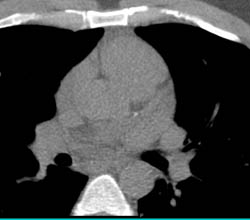

Vessel Analysis to Determine Plaque Composition